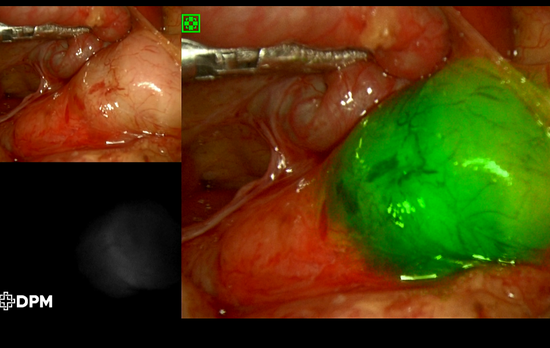

造影提示十二指肠梗阻 术中见梗阻部位为十二指肠降部,梗阻原因为环状胰腺

术中见梗阻部位为十二指肠降部,梗阻原因为环状胰腺02 那么快速康复有是什么呢?

快速康复治疗,又称为快速康复手术(ERAS)或快速通道手术,是一种综合性的医疗策略,旨在减轻手术患者的痛苦,缩短住院时间,提高康复速度,并降低并发症的风险。这种治疗方法通过协调多个医疗专业领域的实践,以最小化手术的身体冲击和恢复期,提高患者的整体术后体验。快速康复治疗的目标是改善患者的手术体验,降低术后并发症风险,缩短住院时间,减少医疗费用,并加速康复过程。快速康复除了需要尽可能的采取微创手术外,还要求术后早期喂养。新生儿肠壁薄,容易发生吻合口漏,采取快速康复治疗需要对于手术吻合技术的高要求。近年来,西安市儿童医院新生儿外科为了更好的以患儿为中心,为了减少患儿痛苦,减少患儿费用,引起世界先进的快速康复理念,在新生儿患儿的术后采用了快速康复理念,采用了相应的医疗护理策略,使这类患儿术后的进食时间由原来的1周左右缩短到术后2天,大大减少了患儿康复的速度。

超声显示双泡征近年来随着微创技术的发展,这些孩子的手术都可以通过腹腔镜技术来实现了。腹腔镜十二指肠梗阻的手术仅需要3个3mm-5mm的小孔。手术后不光微创,术后恢复快。